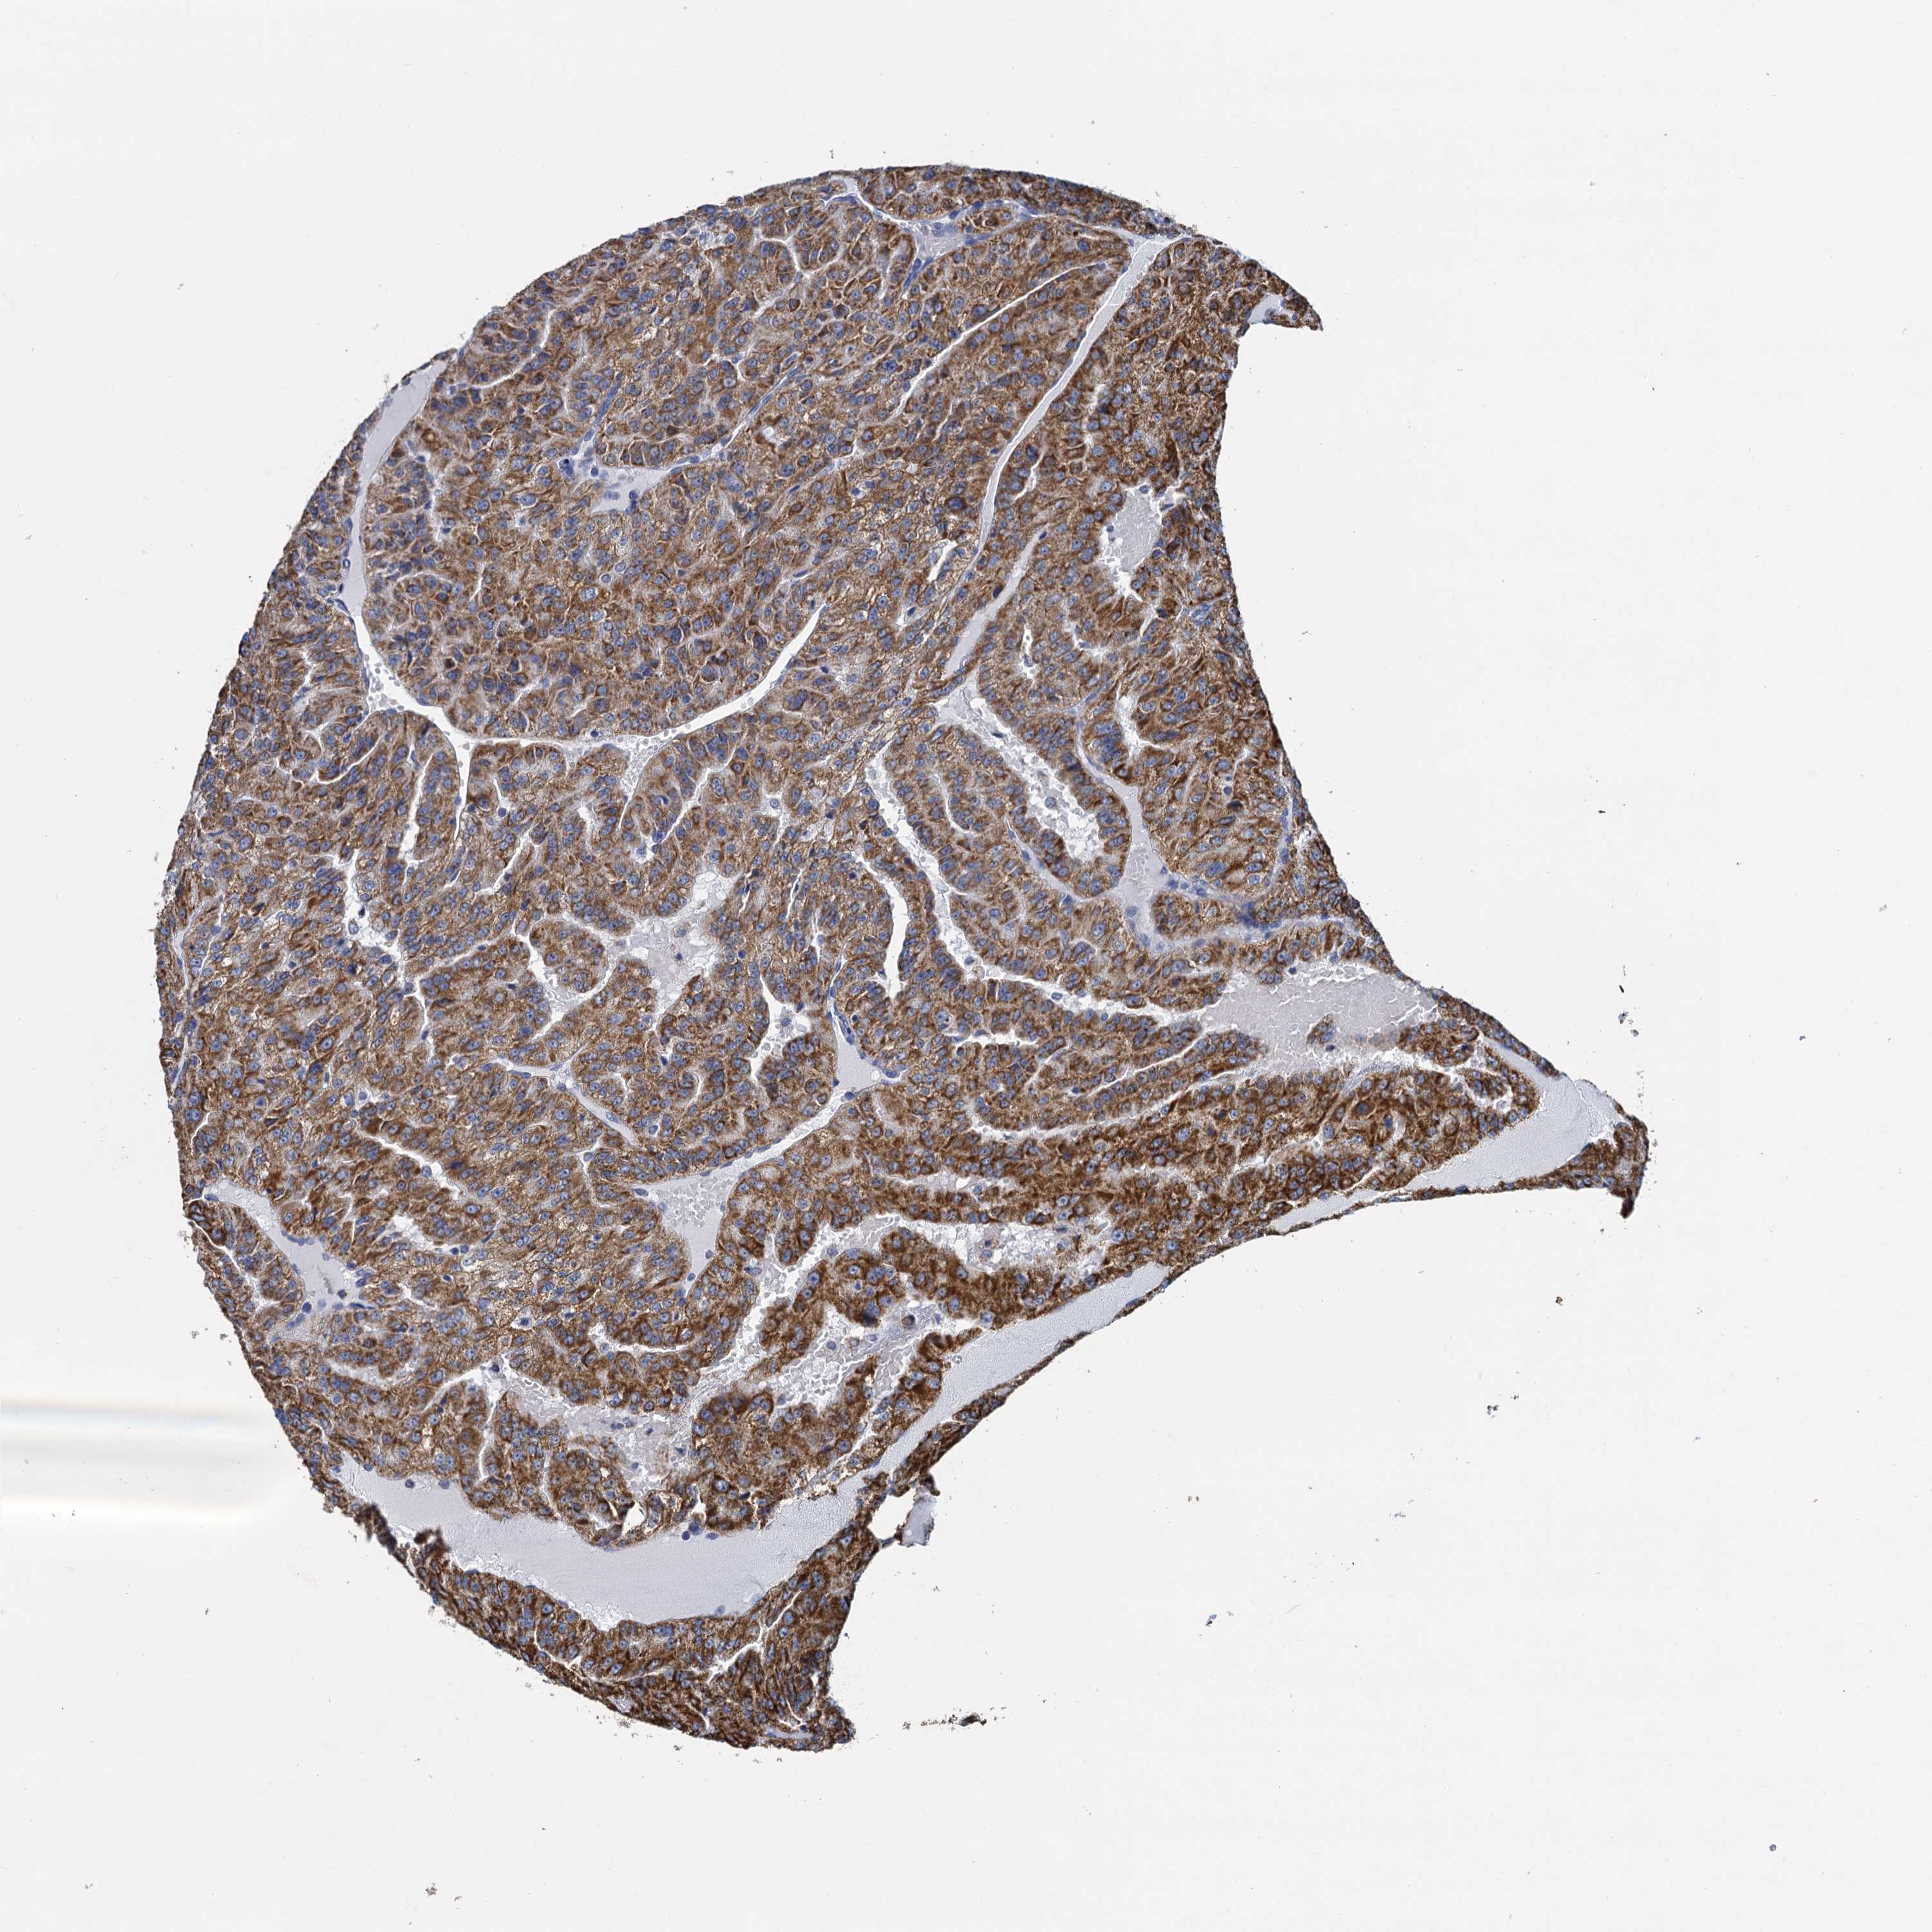

KIDNEY RENAL CLEAR CELL CARCINOMA (VALIDATION) - Interactive survival scatter ploti

The Survival Scatter plot shows the clinical status (i.e. dead or alive) for all individuals in the patient cohort, based on the same data that underlies the corresponding Kaplan-Meier plots. Patients that are alive at last time for follow-up are shown in blue and patients who have died during the study are shown in red.

The x-axis shows the expression levels (FPKM) of the investigated gene in the tumor tissue at the time of diagnosis. The y-axis shows the follow-up time after diagnosis (years). Both axes are complimented with kernel density curves demonstrating the data density over the axes. The top density plot shows the expression levels (FPKM) distribution among dead (red) and alive patients (blue). The right density plot shows the data density of the survived years of dead patients with high and low expression levels respectively, stratified using the cutoff indicated by the vertical dashed line through the Survival Scatter plot. This cutoff is automatically defined based on the FPKM cutoff that minimizes the p-score. The cutoff can be changed by dragging the vertical line or by entering a cutoff value in the square labeled "Current cut-off".

Under the Survival Scatter plot the p-score landscape (black curve; left axis) is shown together with dead median separation (red curve; right axis). Dead median separation is the difference in median mRNA expression between patients who have died with high and low expression, respectively. It is calculated as follows: median FPKM expression of dead patients with high expression - median FPKM expression of dead patients with low expression. This is intended to aid the user in visually exploring custom cutoffs and the associated p-scores and dead median separation.

Individual patient data is displayed and can be filtered by clicking on one or more of the category buttons on the top of the page. Categories describing expression level and patient information include: high, low, alive, dead, female, male and tumor stages. The scale of the x-axis can be toggled between linear and log-scale by clicking on the "x log" button. Mouse-over function shows TCGA ID, patient information and mRNA expression (FPKM) for each patient.

& Survival analysisi

Kaplan-Meier plots summarize results from analysis of correlation between mRNA expression level and patient survival. Patients were divided based on level of expression into one of the two groups "low" (under cut off) or "high" (over cut off). X-axis shows time for survival (years) and y-axis shows the probability of survival, where 1.0 corresponds to 100 percent.

CCP110 is validated prognostic, high expression is favorable in Kidney Renal Clear Cell Carcinoma (validation)

Best expression cut offi

Based on the FPKM value of each gene, patients were classified into two groups and association between prognosis (survival) and gene expression (FPKM) was examined. The best expression cut-off refers the FPKM value that yields maximal difference with regard to survival between the two groups at the lowest log-rank P-value. Best expression cut-off was selected based on survival analysis .

When clicking on this number, the vertical dashed line indicating cut-off, the interactive survival plot, and the Kaplan-Meier curve will be adjusted to show results based on the best expression cut-off.

: 9.66

TCGA RNA samplesi

RNA-seq data is reported as average FPKM (number Fragments Per Kilobase of exon per Million reads), generated by the The Cancer Genome Atlas (TCGA) .

Normal distribution across the dataset is visualized with box plots, shown as median and 25th and 75th percentiles. Points are displayed as outliers if they are above or below 1.5 times the interquartile range. FPKM values of the individual samples are presented next to the box plot.

Average pTPM 8.6

Number of samples 100